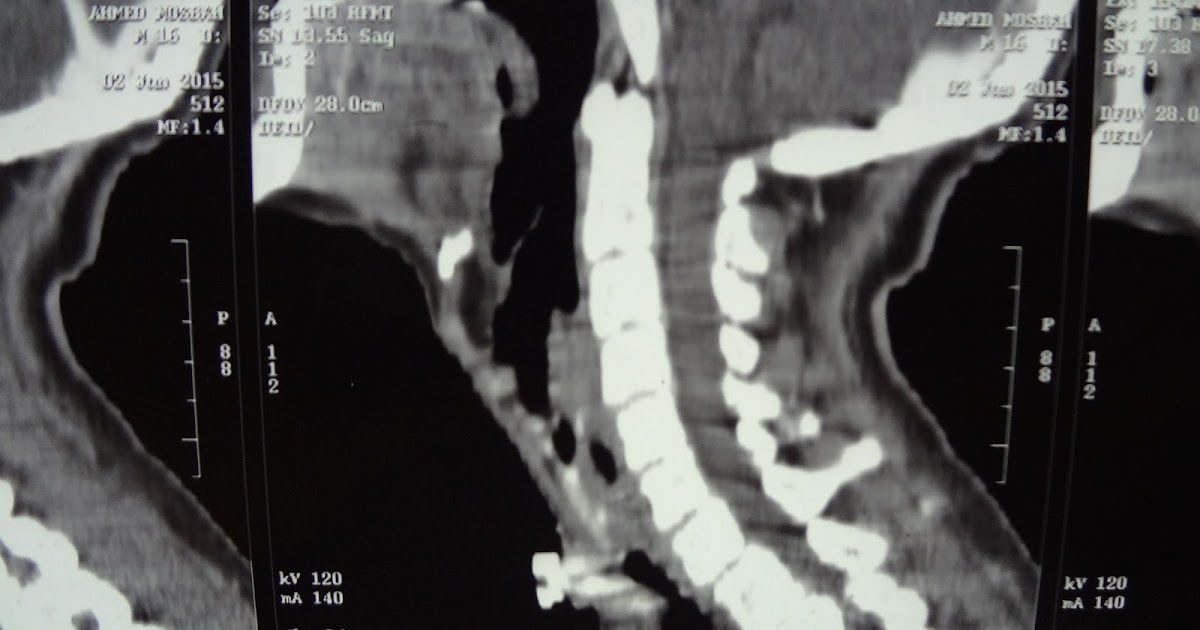

From rubbuy781.blogspot.com

laryngeal tracheal stenosis grade IV . UPPER airway stenosis due to Tracheal Stenosis In Endotracheal Intubation Thus, tracheal stenosis can most commonly occur following the two types of airway intubation: Tracheal stenosis is a common complication of endotracheal intubation or tracheostomy, resulting in significant morbidity. Tracheal stenosis, a common respiratory condition, is often caused by tumour or tuberculosis, or is a complication of intubation. Although infraglottic stenosis most commonly results from endotracheal tube damage, it may. Tracheal Stenosis In Endotracheal Intubation.